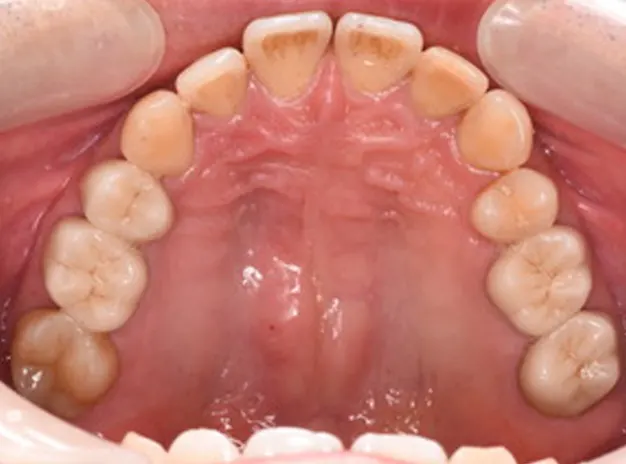

40歳男性

全身の痒みと金属の除去

上顎両側奥歯部

6ヵ月

仮歯:6,000円×4本

ファイバーコア:5,500円×3本

オールセラミッククラウン(奥歯):110,000円×4本

ポーセレンインレー:1本

合計:546,500円(税込)

以前より全身に痒みを訴え、口腔外科より金属アレルギーの改善のため大桑歯科受診を勧められて来院。口腔外バキュームやラバーダム防湿で銀歯撤去時に金属片が飛散しないようにコントロールしながらメタルを撤去し仮歯へ置き換えました。金属がお口から少なくなるにつれて体調が良く痒みもずいぶん少なくなってき様子でした。将来の再治療をなくすためにも、丈夫で長持ちするジルコニアにて最終的な被せ物を作成しました。セラミック治療後は体の痒みや発赤がなくなり、人生が変わったようだと非常に喜んでおられました。